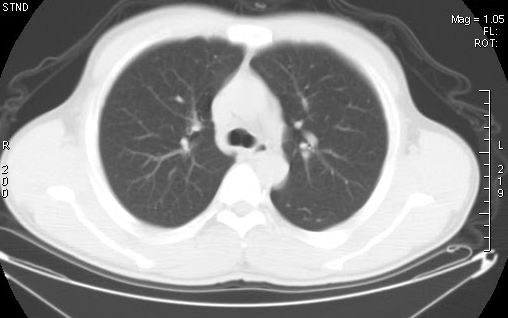

标题: CT7610:[原创]右上纵隔还是肺内占位,请会诊!

体检发现,无任何不适。

右肺见纵隔旁见类圆形界清等密度肿块影,直径约5.0cm,增强呈不均匀强化,重建的图片上看到肿块内可见强化的血管影,考虑:1,肺腺瘤;2,肺肉瘤。